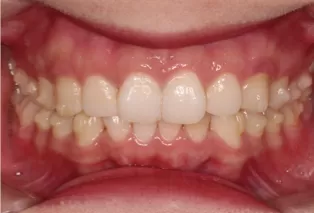

Intraoral photos